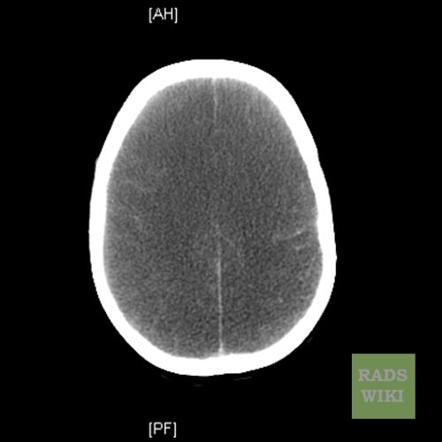

Huntington’s disease

atrophy of caudate head causes enlargement of frontal horns